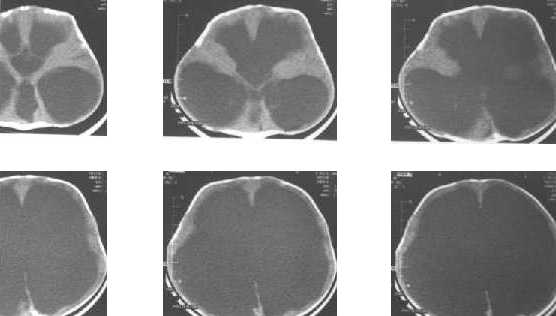

Congenital hydrocephalus, Communicating : huge